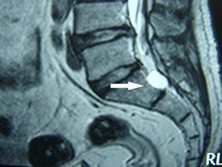

骶管囊肿属于硬脊膜囊肿,起源于脊髓膜,因此使用椎管内脊膜囊肿一般来说,这种疾病。...

脊柱CT、脊柱MRI、X线平片